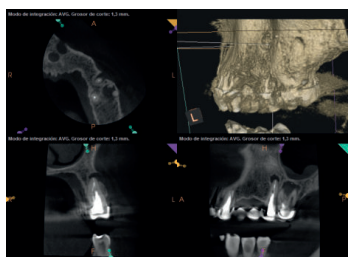

Para confirmar el origen endodóntico y el tamaño de las lesiones se realizaron exploraciones tomográficas con espesor de corte de 75 micras mediante CBCT CS8100 (Carestream Dental® ) en las que se evidenciaron lesiones periapicales radiolúcidas a nivel de 12, 11, 21 (con afectación bicortical), 25 y raíces vestibulares de 26 (Figuras 4 a 8).

Por otra parte, las raíces vestibulares del 26 presentaban un tratamiento de conductos claramente deficiente, con subextensión de varios milímetros, así como conducto mesiopalatino (MP) omitido; por lo que se planteó al paciente la necesidad de reendodonciar dichas raíces, antes de realizar la microcirugía del 25 (Figura 9).